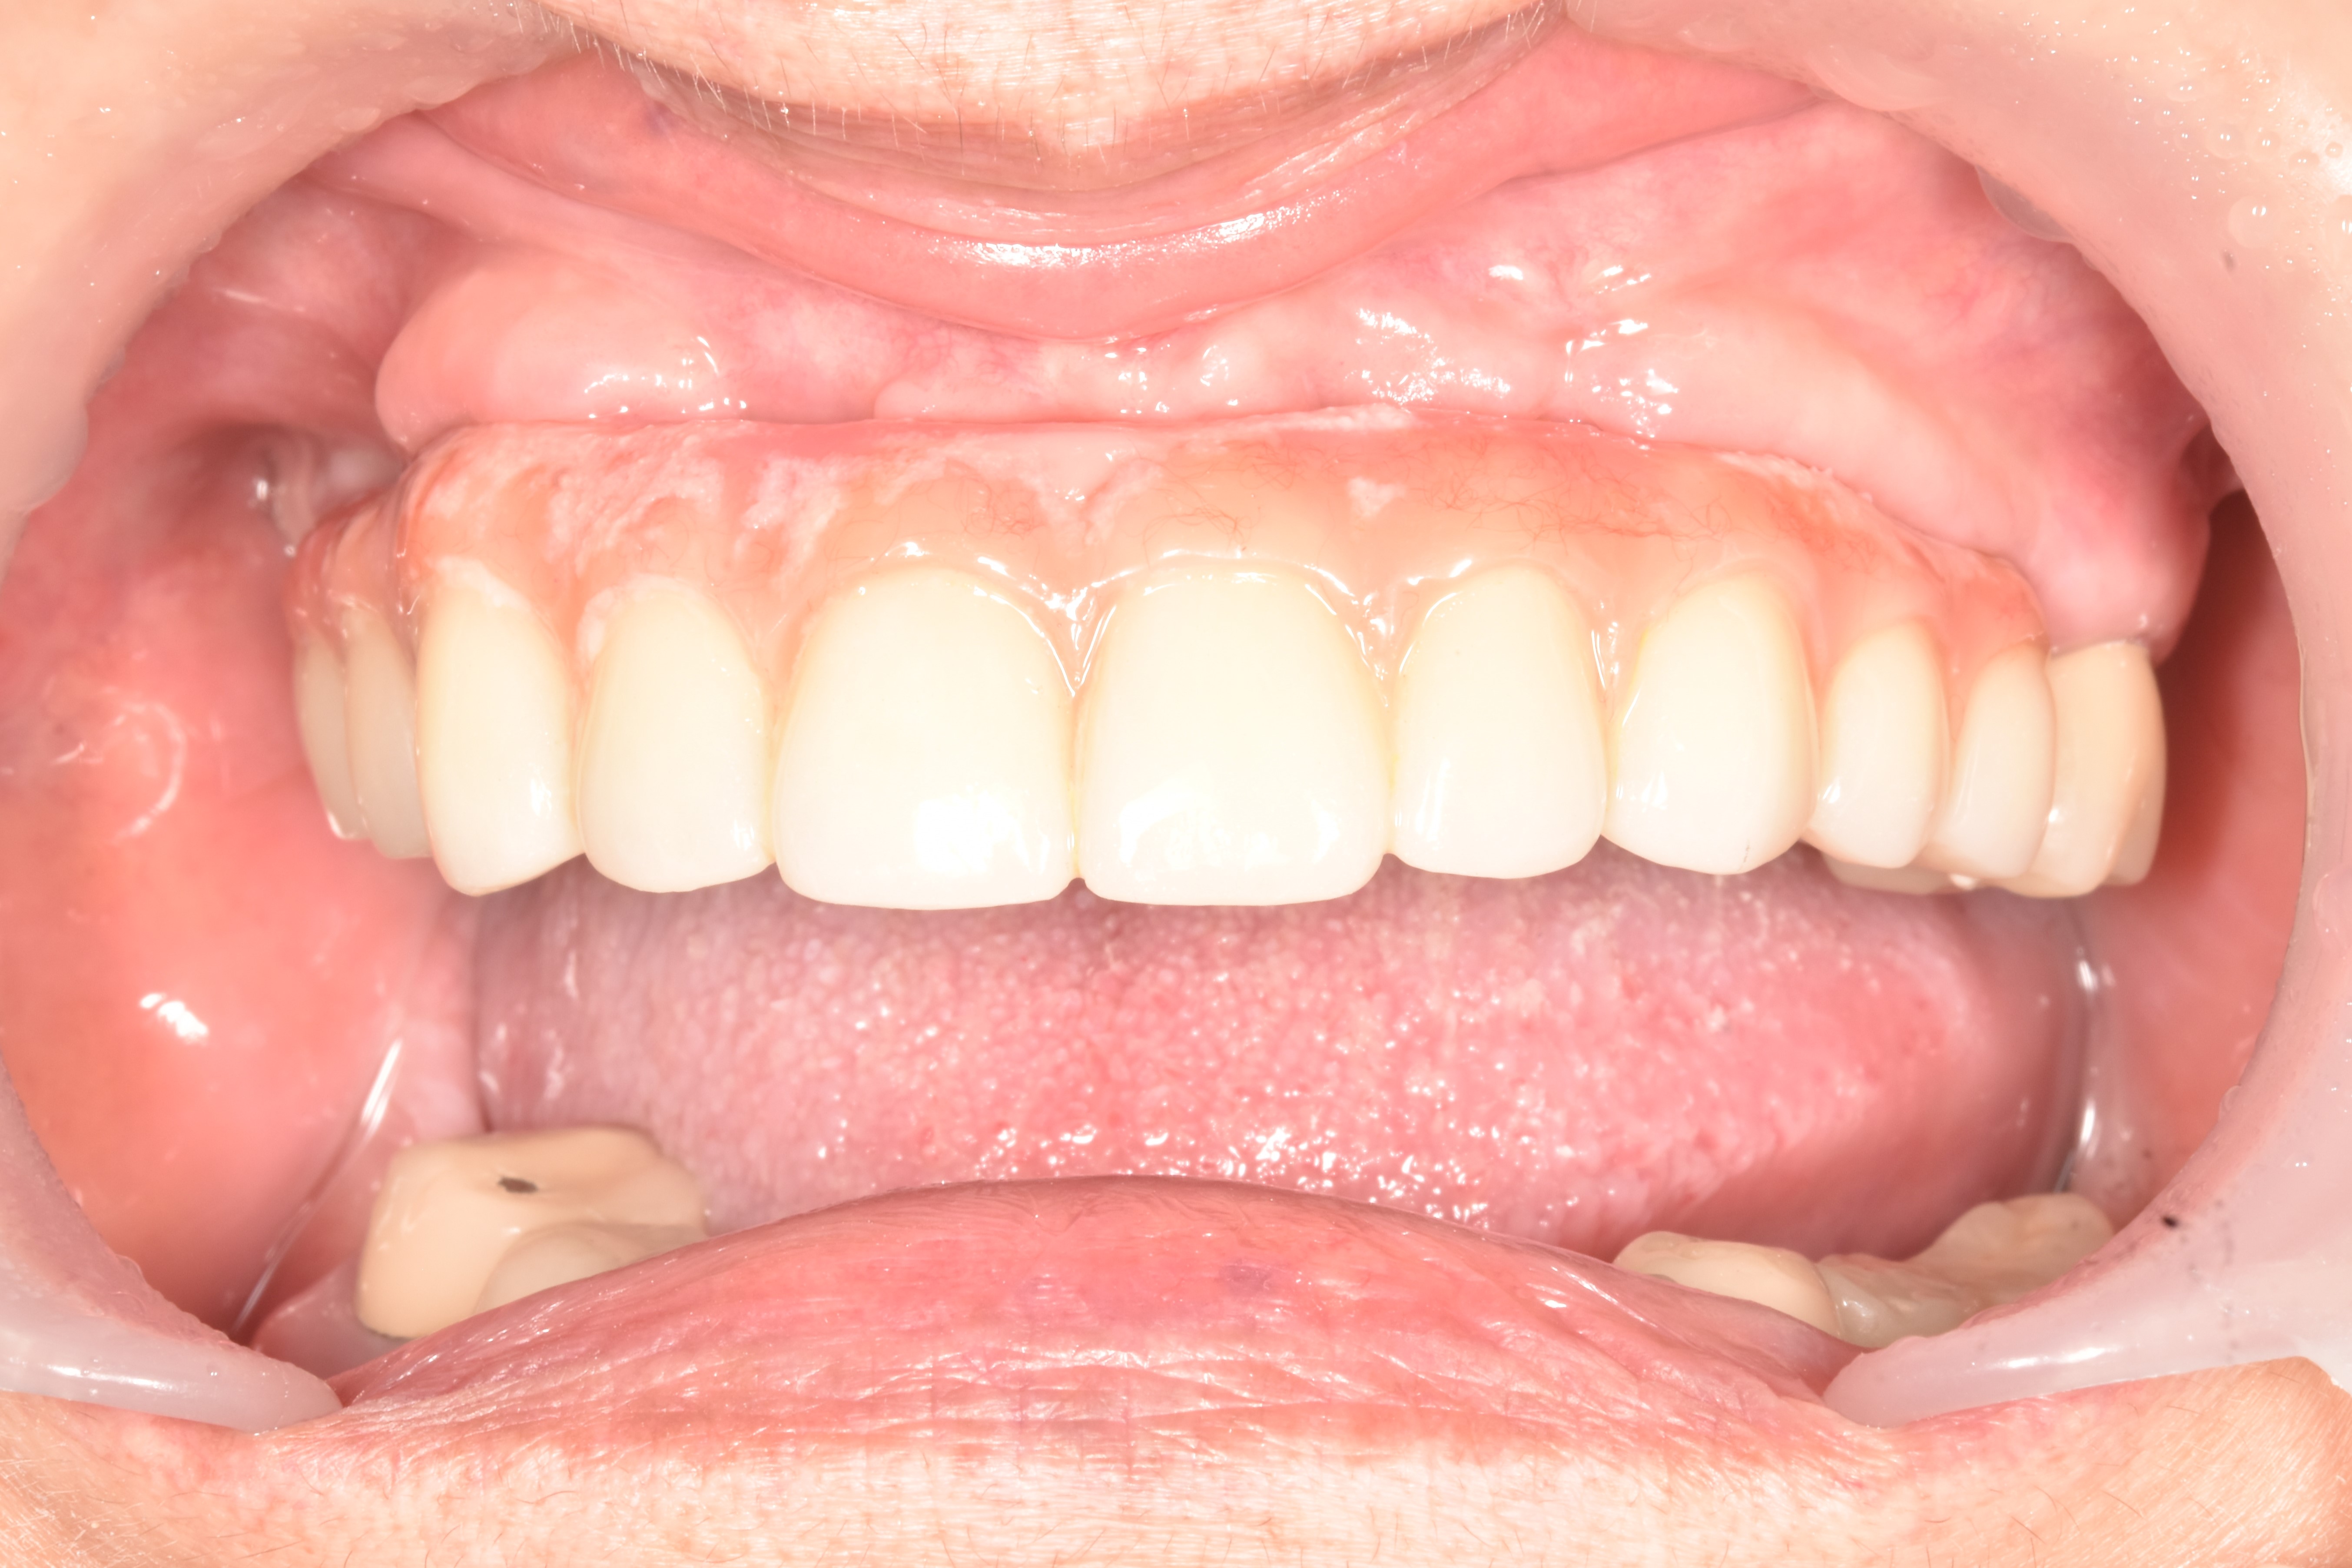

All on 4 / All on X